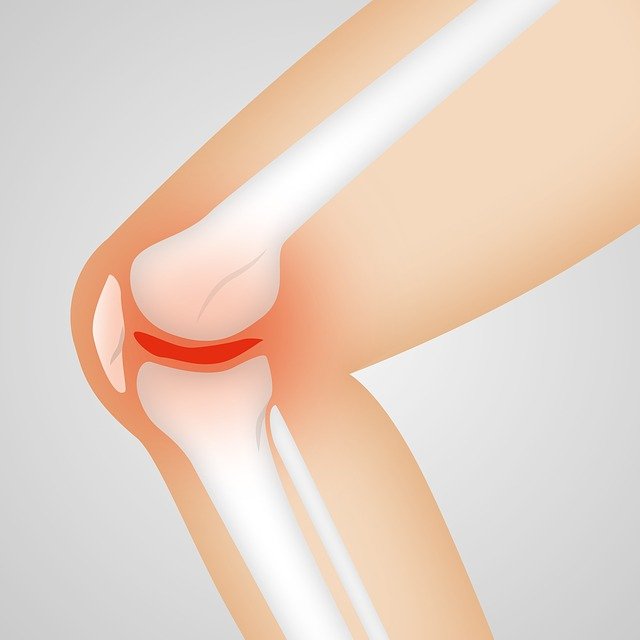

2. 관절 부어오름

류마티스 관절염 초기 증상 두 번째는 관절이 부어오르는 것으로 염증으로 인해서 관절에 물이차 오르며 점차 부어오르게 됩니다. 만약 방치할 경우 손가락에 기형이 올 수 있으니 병원을 방문해서 치료하는 것이 좋습니다.